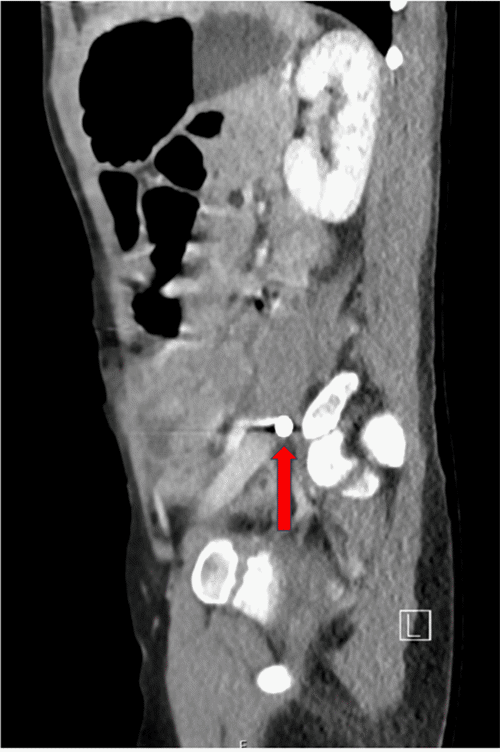

Given the patient’s stability and the localized nature of the injury, a CT scan was performed for further evaluation. Imaging studies were significant for retained foreign body lodged within the left psoas muscle (Figure 1). Additionally, the CT scan helped visualize the projectile’s trajectory from the anterior abdominal wall to the left psoas muscle. This trajectory confirmed a heightened suspicion for violation of the viscera. At this point, the decision was made to proceed with operative intervention due to the trajectory of the injury despite the absence of free air or free fluid in the radiographic interpretation.

Figure 1. Axial and Sagittal CT Abdomen & Pelvis. Published with Permission

(B) Sagittal view of CT abdomen and pelvis showing the retained 9mm ballistic fragment